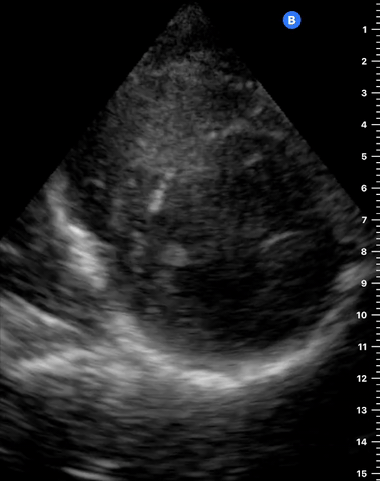

A correct PLAX view will align with the heart’s long axis, producing a sagittal cut. On the screen, from the top, we see the right ventricle, the interventricular septum, the left ventricle with its outflow tract, the aortic valve and aortic root, and the left atrium. It is essential to look for the descending aorta, which appears in a transversal cut deeper to the LV.